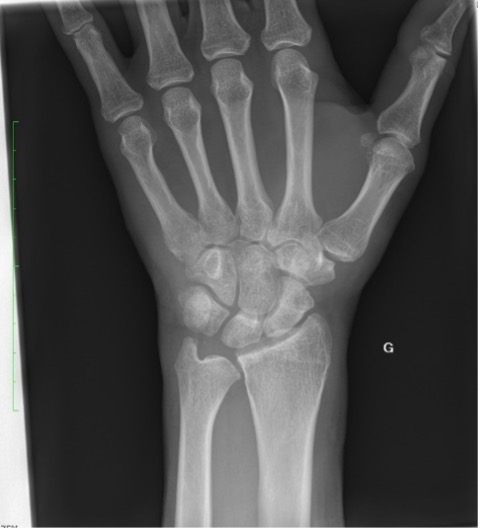

Un patient se présente pour des douleurs au niveau du poignet gauche, suite à une chute à vélo avec réception sur la paume de la main. Cliniquement, nous observons un œdème au niveau du dos de la main, des douleurs à la mobilisation du poignet avec une discrète limitation de l’extension et une prono-supination conservée.

La radiographie effectuée révèle une fracture du triquétrum. Les fractures du triquétrum (ou os pyramidal) sont les fractures du poignet les plus fréquentes après celles du scaphoïde, représentant 13% des fractures des os du carpe. Elles résultent habituellement d’une chute sur la main en hyperextension et déviation ulnaire. Elle est fréquemment retrouvée chez des pratiquant·es de sports de combat.

Il existe trois types de fractures du triquetrum : les fractures corticales dorsales, les fractures du corps et les fractures corticales palmaires. Pour ce patient, il s’agit d’une fracture de type 1 (95% des cas), qui est une fracture par avulsion associée à des lésions des ligaments dorsaux du carpe et considérée comme une « entorse grave du poignet ».

La clinique est aspécifique mais le diagnostic doit être évoqué face à des douleurs sur le côté ulnaire du carpe, après une chute main en extension. Les fractures du triquetrum passent facilement inaperçues sur les radiographies conventionnelles du poignet, mais elles sont souvent associées à des lésions ligamentaires importantes conduisant à une instabilité du carpe, ou évoluent vers une pseudarthrose. Un complément par CT (ou IRM) peut être nécessaire afin de confirmer le diagnostic et préciser les lésions.